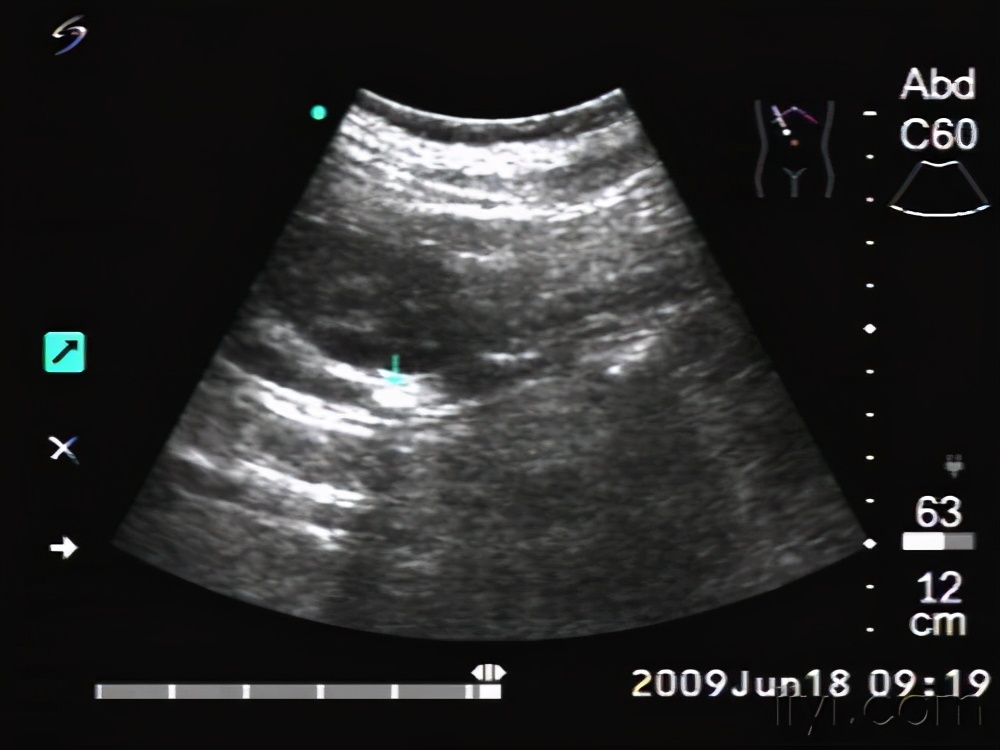

B超检查视:右肾90×45mm集合系统分离20mm ,右输尿管上端扩张12mm,距输尿管开口处20mm见6mm光团伴声影。

诊断: 右肾盂积水,输尿管扩张伴结石